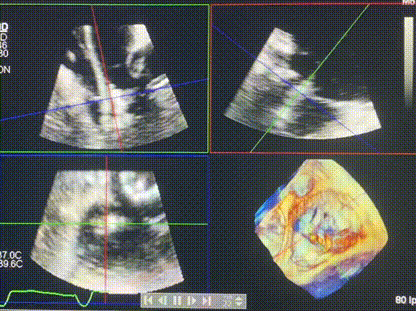

術(shù)中輸送器在超聲引導(dǎo)下調(diào)整位置

手術(shù)在全麻狀態(tài)下進(jìn)行。術(shù)者采用經(jīng)右側(cè)頸靜脈入路的方式將輸送器送入患者心臟內(nèi),在TEE及DSA引導(dǎo)下調(diào)整輸送器頭端角度,使得輸送器與三尖瓣瓣環(huán)平面垂直。在輸送器進(jìn)入右心室后釋放室間隔錨定裝置,而后釋放瓣葉夾持件(2個(gè)耳片結(jié)構(gòu))成垂直狀態(tài)。在TEE及DSA確定夾持件固定至三尖瓣葉根部且位于右室側(cè)后釋放人工瓣心房側(cè)盤片。隨后調(diào)整瓣膜同軸性以及室間隔錨定件位置(貼合室間隔),前推藏針管并固定,進(jìn)而釋放室間隔錨定裝置,并再次確認(rèn)瓣膜位置、穩(wěn)定性及同軸性,合攏輸送鞘后撤出輸送器,完成LuX-Valve Plus人工三尖瓣瓣膜的植入,僅殘余微量瓣周漏。且經(jīng)手術(shù)中心電生理團(tuán)隊(duì)評(píng)估,病人的起搏器和ICD功能沒(méi)有受到影響。